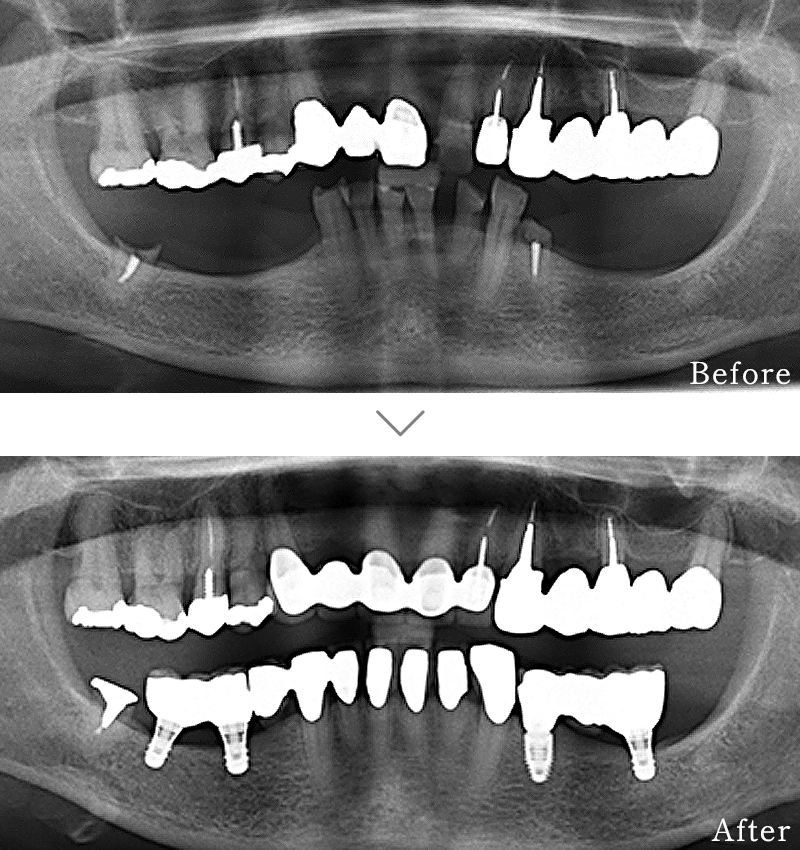

CASE1

主訴 入れ歯も合わず、しっかりと噛んで食事ができないとのことで来院されました。

治療法 上下ともにALL-ON-6と呼ばれる最少本数のインプラントで全ての歯を回復する治療を行なっています。歯の部分は全てセラミックで作成されています。

治療期間 5ヶ月

費用 CT:16,500円(税込)

+ 静脈内鎮静法:66,000円(税込)

+ ALL-ON-6×2:5,500,000円(税込)

合計:5,582,500円(税込)

副作用

• 歯周病に感染・発症し重度に進行するとインプラントが抜けてしまうことがあります。

• 手術後は数日間腫れが出る場合があります。